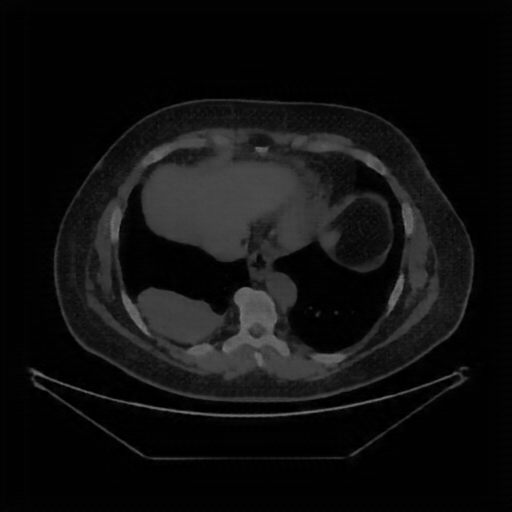

Image Grid

4×3 grid: Rows show different image types (Original NATIVE, Reconstructed NATIVE, Original VENOUS, Generated VENOUS), Columns show windowing techniques (No Window, Lung Window, Mediastinum Window)

Original NATIVE CT scan (input)

No window - Raw intensity values

Original VENOUS CT scan

No window - Raw intensity values

Original VENOUS CT scan

Lung window (WL -600, WW 1500 → Low −1350, High +150)